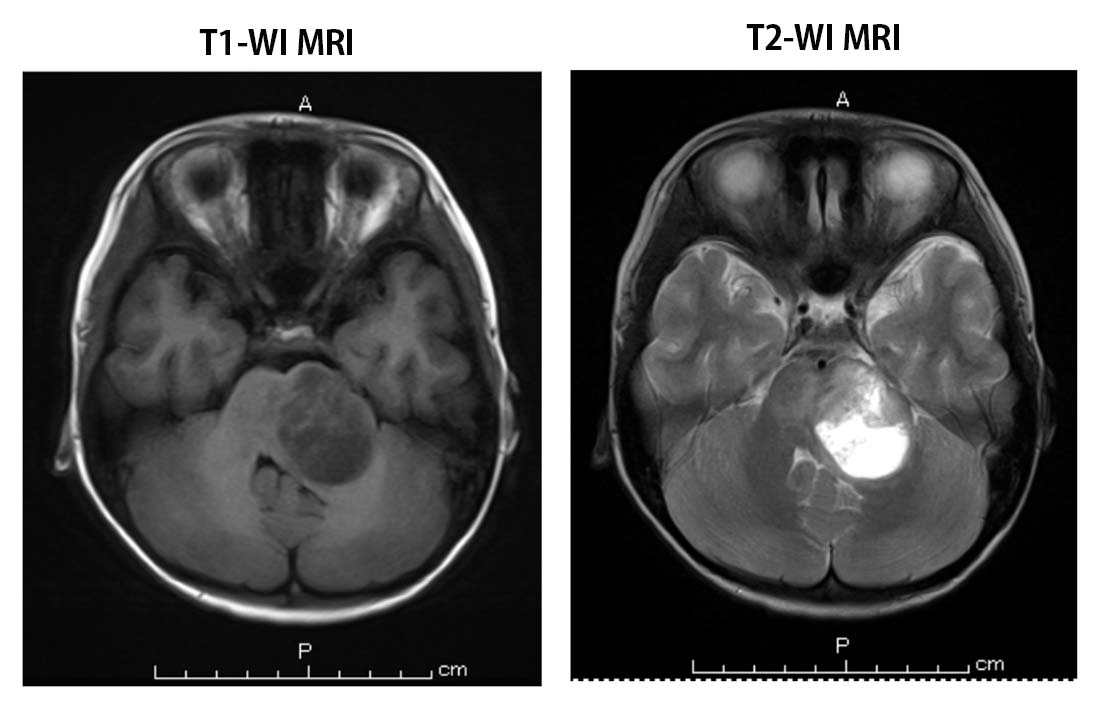

Case 03--5.8yo boy-WHO2016のレベルでもPending になるケース.

T-Case.jpg

一見するとparagangliomaみたいな, oligodendroglial-like cellのような細胞がはいってきてsynaptophysin(+), GFAP部分+でもしかしたらglioneural tumorかなというcase.

OLIG2+, MAP2,S-100(+), GFAP(+/-), synaptophysin(+)

differential diagnosis

Final, integrated diagnosis

Integrated diagnosis: Pending WHO2016レベルでもpendingの腫瘍

Histological diagnosis: Diffuse leptomeningeal glioneuronal tumor

Histological grade: Grade ?

Molecular information: IHC: positive for synaptophysin, GFAP, negative for S-100

Diffuse leptomeningeal glioneuronal tumorという, 新しく加わった腫瘍で予後のはっきりしない, しかし顕微鏡レベルやMRIレベルでみるととてもじゃないけど予後不良だなというdisseminationしている腫瘍.細胞成分としてはそんなに悪くない.

今このWHOレベルでもintegrated diagnosisはpending。Histological diagnosisとしてははっきりいえる。まだまだ症例が足らなくて, もうすこし症例を集めてgradeを検討しよう。これから先は, molecular informationについては調べていきましょうということです。これでも正式な診断書というレベルの腫瘍も新しく加わった腫瘍にはあるんですね。